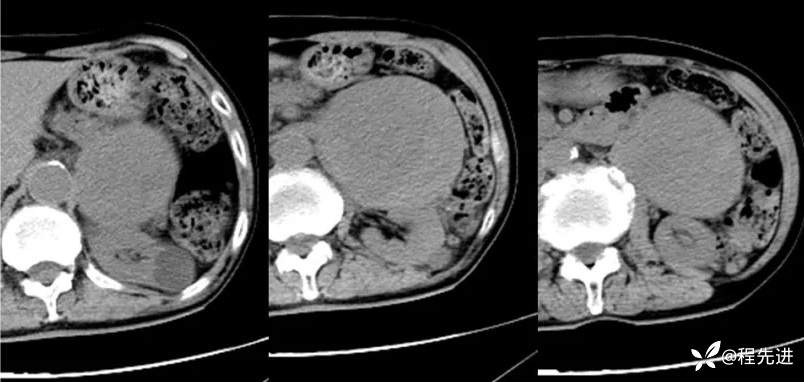

CT平扫: